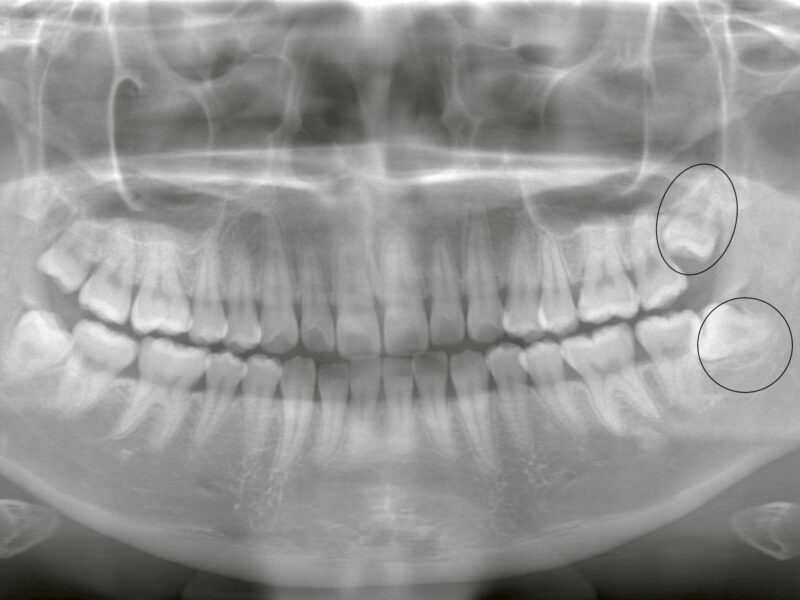

特徴4高精度診断を可能にする「歯科用CT」 -